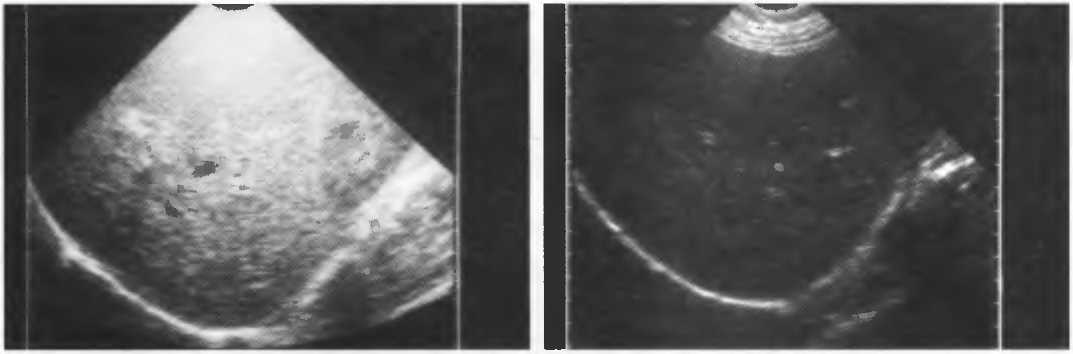

Рис.13б. Эхография печени. Слева: общее повышение чувствительности. Справа: общее понижение чувствительности.

Рис.13в. Эхография печени. Слева: слабое усиление срединных отделов печени, справа: правильная регулировка, усиление по глубине.

Рис.13е. Слева: плохая визуализация в результате слишком высокого усиления передних отделов; сравните нечеткое изображение передней части головки с достаточно четким изображением задних отделов (сравните рис. 13ги 13д;. Справа: регулировка по глубине была изменена; теперь определяется слишком низкое усиление близких структур и слишком высокое усиление глубокорасположенных структур.

Можно производить также регулировку чувствительности прибора в зависимости от глубины расположения объекта сканирования (рис. 14д-е).

Рис.14д. Изображения головки плода. Слева: сбалансированное по глубине изображение, общая чувствительность низкая. Справа: чувствительность прибора в ближних отделах сильно завышена; ее необходимо уменьшить, в то время как общая чувствительность должна быть увеличена с тем, чтобы можно было визуализировать всю головку.

Рис. 14е. Слева: хорошо сбалансированное изображение. Справа: чувствительность в глубоких отделах необходимо уменьшить, а в близкорасположенных отделах — увеличить.